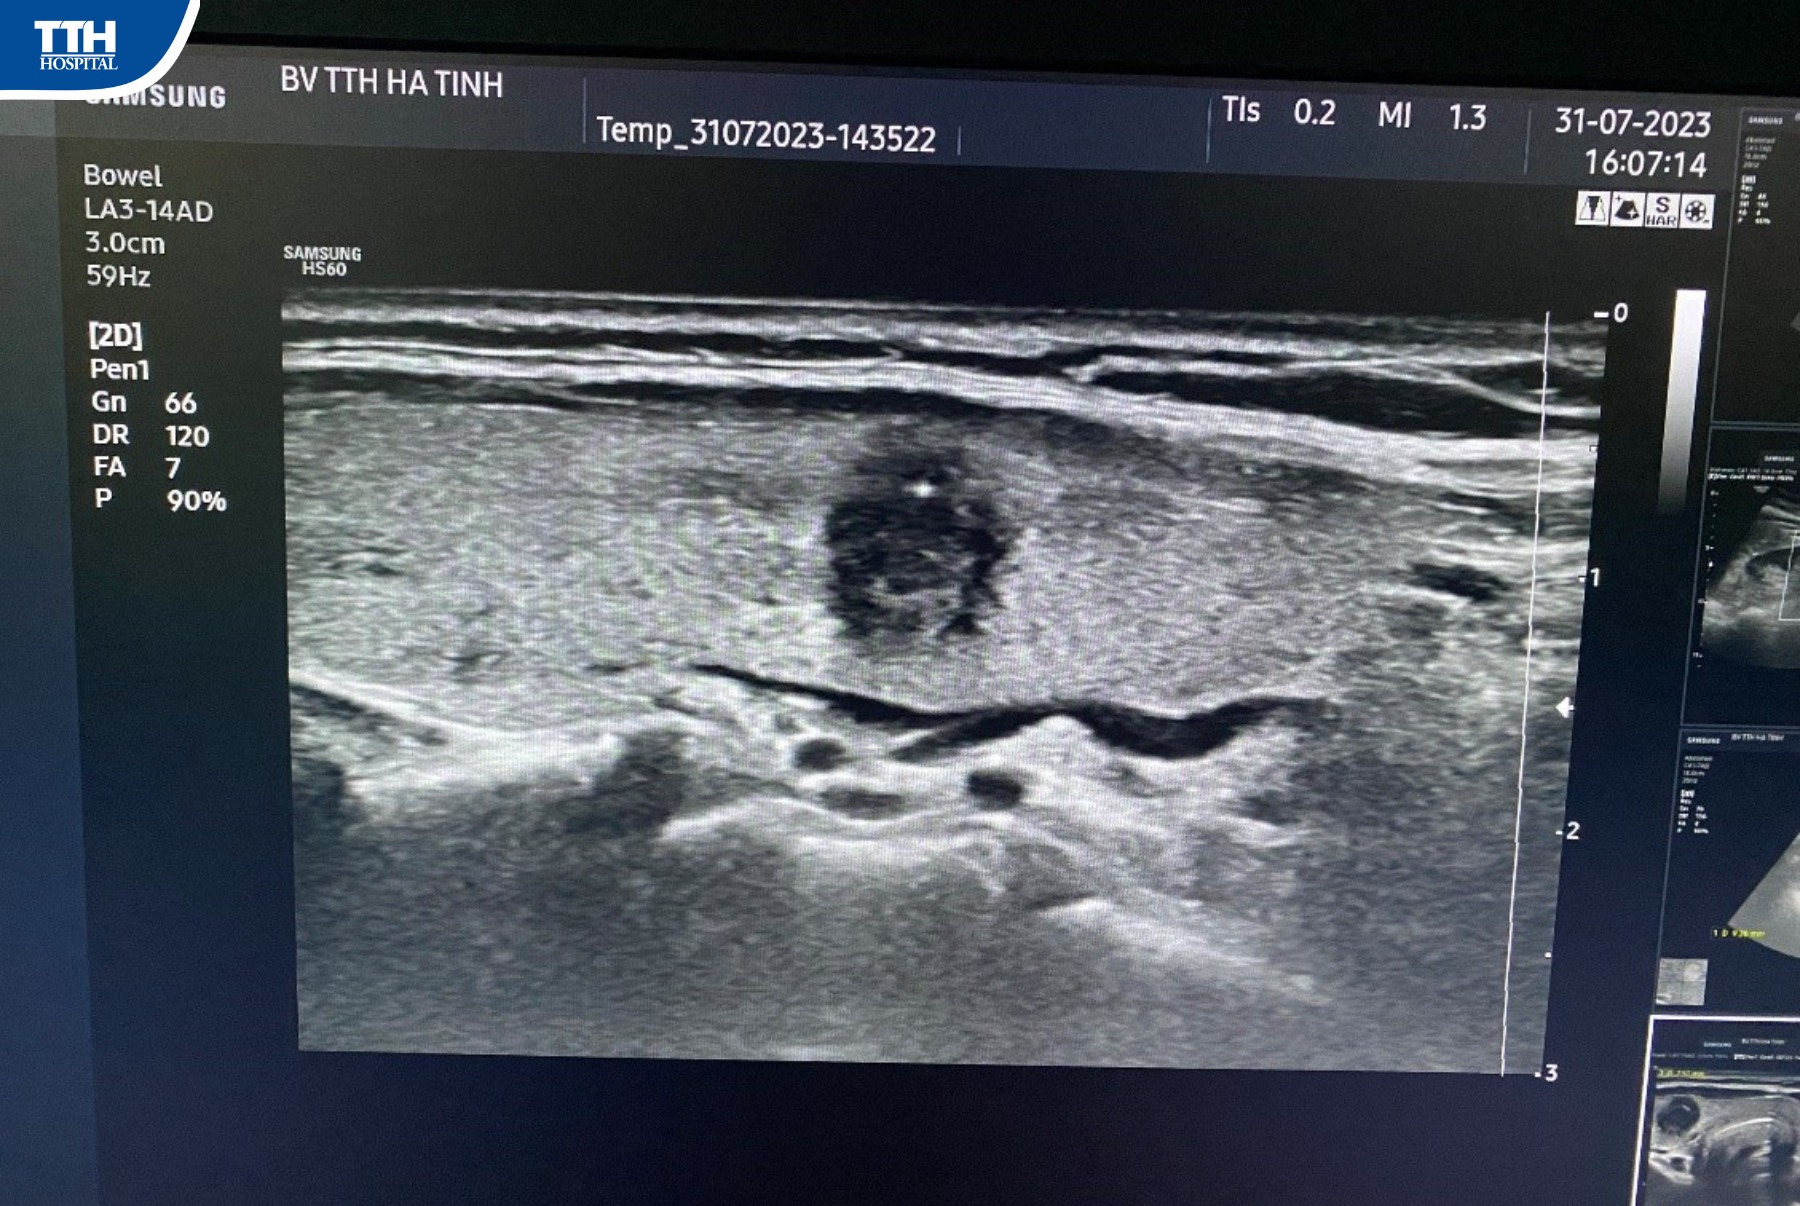

Bệnh nhân Đ.T.H 45 tuổi, trú tại Kỳ Anh, Hà Tĩnh và bệnh nhân P.T.H 38 tuổi, trú tại Hương Sơn, Hà Tĩnh đến Bệnh viện Đa khoa TTH Hà Tĩnh khám sức khỏe không có triệu chứng gì. Tại đây, bệnh nhân được bác sĩ Trinh thực hiện siêu âm tuyến giáp và tình cờ phát hiện nhân nhỏ tuyến giáp kích thước khoảng 0,7x0,5cm, nhân rất giảm âm, trục dọc, bờ không đều, có nốt vi vôi hóa, xếp loại TIRADS V, kết quả sinh thiết “ung thư tuyến giáp”. Sau đó, bệnh nhân đã được điều trị kịp thời, ngăn chặn bệnh tình chuyển biến phức tạp hiệu quả nhờ tầm soát phát hiện sớm.